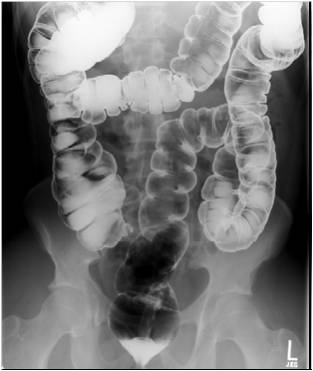

Double-contrast irrigoscopy.

Fig.23.: Radiographic image: multiple, round filling defects are seen on the sigma and on the descending colon.

Image

Fig.24.: Double-contrast irrigoscopy